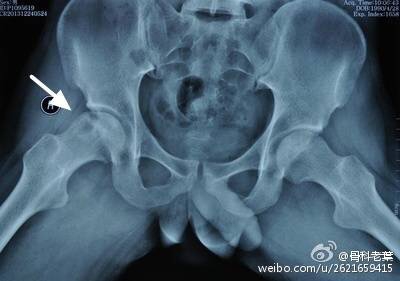

II期 病人有髋部症状,磁共振出现异常,X线片显示股骨头出现透光和硬化改变

II期和III期的患者治疗方法相同,因为此时股骨头虽然还没有变形,暂时还不需要行人工关节置换术,但是股骨头已经出现空洞,随时股骨头就会塌陷变形,所以单纯的股骨头减压术是不能达到治疗效果的。这时就需要在股骨头减压的同时,植入一根支撑棒,顶住股骨头空洞区,防止股骨头在负重的情况下过早塌陷。其他治疗同之前相同,口服以上药物,定期复查,密切观察病情发展,尽量避免重体力劳动和爬山爬楼。